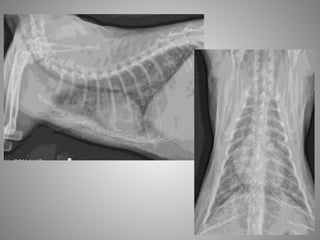

• #15 All these previously discussed changes – stim of SNS, stim of RAAS and fluid retention only occur with SEVERE heart disease. The heart does not fail with mild or moderate changes. Thus animals with MMVD or HCM must have a severely enlarged LA to be in HF. The only exception to this is acute chordal rupture in MMVD in which case there will be severe respiratory signs and a suddenly loud murmur. In DCM there should be severe systolic dysfunction (CHF not likely if FS > 15%) Anything less severe than this, and the dog or cats signs are unlikely due to CHF and other causes of clinical signs should be sort. Thus, sometimes diagnosing CHF can be more difficult than one would think. 1st image – cat with respiratory signs, alveolar pattern, HCM with severe LAE 2nd Doberman with DCM, cough, increased respiratory rate. Severe systolic dysfunction and marked LAE and LVE

• #22 This is one of the most extreme examples of left atrial enlargement without CHF that I have seen. This was a older small breed dog whom presented with chronic cough Despite the extreme LA enlargement, the lung fields are completely clear and the pulmonary veins are small indicating that this dog is not in heart failure. Hence, frusemide is not warranted in this patient. This dog was part of a study I performed during my cardiology training looking at dogs like this. Those that had a heart murmur due to MMVD and a chronic cough but weren’t in CHF. If we look closely at this this radiograph, we can see collapse of the mainstem bronchi on the lateral view and severe collapse of the left lower airways on the DV

• #23 In this study, 10 dogs with mod- severe LAE due to MMVD and chronic cough without CHF were enrolled. These were the study dogs 6 dogs without or with only mild LAE with chronic cough were the control dogs. All dogs had echocardiography, thoracic radiographs, fluoroscopy and bronchoscopy performed in an attempt to try and characterize further the disease process occurring. Historically the cough in this dogs was thought to be due to compression of the left mainstem bronchus and I thought this was going to be the case in my study However, the results of this study led me to question if this syndrome actually exists and to also question now best to treat these dogs.